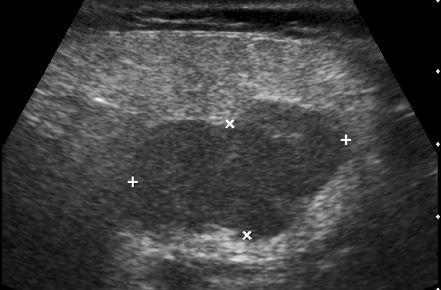

Tubular Ectasia of the Rete Testes

• The rete testes are a complex collection of small tubules that are located in the mediastinum of the testis. Fluid from the seminiferous tubules drains into the rete testis and then exits the rete testis via the efferent ductules. The efferent ductules then converge into the head of the

epididymis.

• Tubular ectasia of the rete testes is believed to be caused by some degree of outflow obstruction of the seminiferous fluid. Perhaps this is the reason why it is frequently associated with testicular cysts and spermatoceles of the epididymal head. It is also more commonly seen in patients with a history of inguinal surgery, such as hernia repairs and vasectomies.

• The key to making the diagnosis and distinguishing tubular ectasia of the rete testes from cystic testicular tumors is to note the bilateral involvement when present and to recognize the elongated shape on long-axis views of the testis.